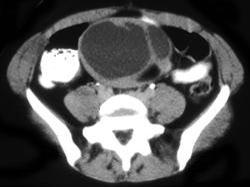

45岁女性患者,自觉腹部胀痛就诊,无发热,血象正常。B超提示左侧附件占位,行CT检查,如图所示,盆腔内见低密度肿块影,其内密度不均,最低CT值约为-150...

问题 45岁女性患者,自觉腹部胀痛就诊,无发热,血象正常。B超提示左侧附件占位,行CT检查,如图所示,盆腔内见低密度肿块影,其内密度不均,最低CT值约为-150.0hu。你认为最佳答案是 ( )

选项 A、卵巢异位妊娠 B、卵巢粘液癌 C、卵巢皮样囊肿 D、卵巢结核 E、卵巢粘液瘤

答案 C